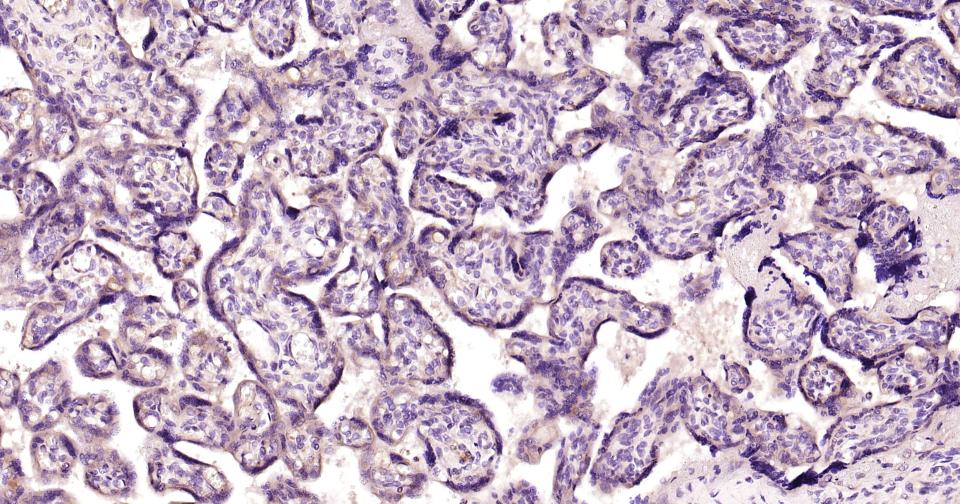

Paraformaldehyde-fixed, paraffin embedded Human Kidney; Antigen retrieval by boiling in sodium citrate buffer (pH6.0) for 15 min; Antibody incubation with LRP2 Polyclonal Antibody, Unconjugated (bs-42103R) at 1:200 overnight at 4°C, followed by conjugation to the SP Kit (Rabbit, SP-0023) and DAB (C-0010) staining.

Paraformaldehyde-fixed, paraffin embedded Human Placenta; Antigen retrieval by boiling in sodium citrate buffer (pH6.0) for 15 min; Antibody incubation with LRP2 Polyclonal Antibody, Unconjugated (bs-42103R) at 1:200 overnight at 4°C, followed by conjugation to the SP Kit (Rabbit, SP-0023) and DAB (C-0010) staining.